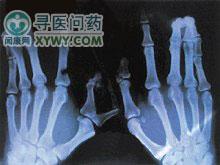

软骨外胚层发育不全(chondroectodermaldysplasia)于1940年首先由Ellis和VanCreveld报道,故常称为Ellis-VanCreveld综合征,多在亲属通婚的家庭中有较高的发病率,属常染色体隐性遗传,中胚层和外胚层组织均受累,常伴随先天性心脏病。